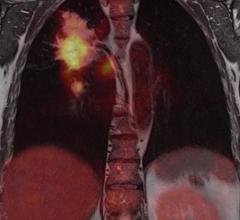

Computer-aided detection software helps doctors make more accurate diagnosis by assisting in the interpretation of medical images.

November 30, 2018 — Big data and artificial intelligence (AI) company Infervision announced the launch of InferRead CT ...